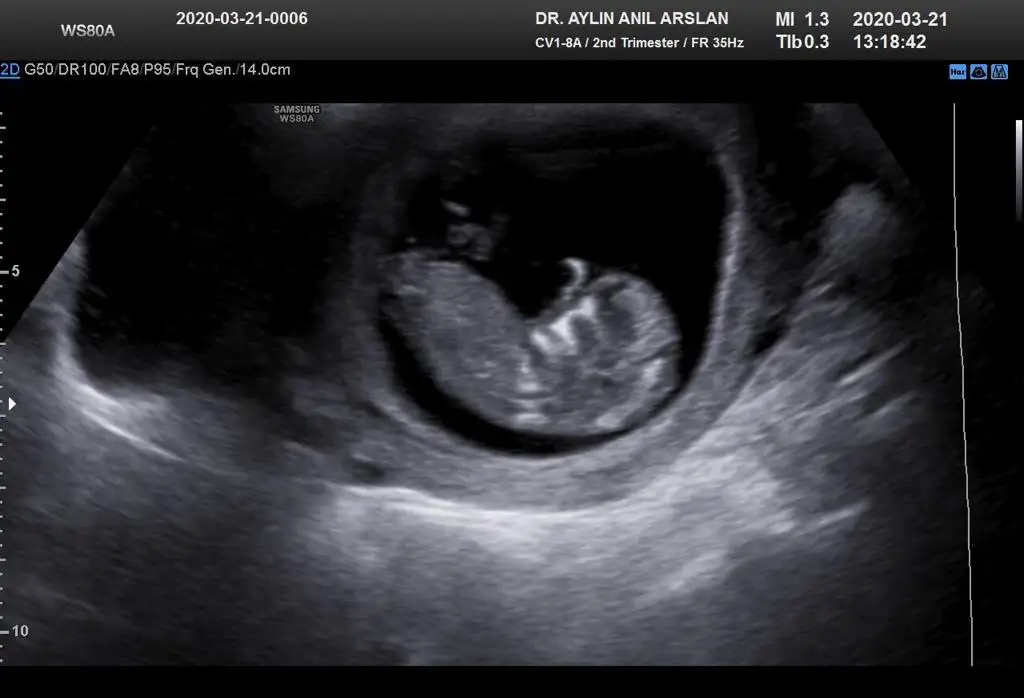

11+3 ama cok net değil gibi sanki yinede Bi tahmin isterim daha 5 hafta sonra öğrencez mecbur 😪

• IMG-20200321-WA0010.webp

IMG-20200321-WA0010.webp

25,9 KB · Görüntüleme: 44

• IMG-20200321-WA0011.webp

IMG-20200321-WA0011.webp

25,8 KB · Görüntüleme: 41

• IMG-20200321-WA0012.webp

IMG-20200321-WA0012.webp

25,8 KB · Görüntüleme: 40

• IMG-20200321-WA0009.webp

IMG-20200321-WA0009.webp

17,6 KB · Görüntüleme: 34

• IMG-20200321-WA0006.webp

IMG-20200321-WA0006.webp

17,6 KB · Görüntüleme: 37